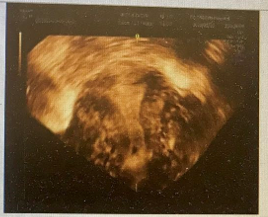

患者丁某,女,35岁,因“发现附件包块10年,经期延长4+年”于2022年1月24日入院 现病史:患者于10年前在外院体检时发现附件包块,自述大小约2+cm,患者无月经改变,无痛经等不适,嘱随访。4+年前无明显诱因出现月经经期延长,由原来5天延长至7-10+天,月经周期及经量无明显改变,患者曾于外院复查B超提示附件区包块无明显改变,遂继续随访。2+年前患者因“腹痛”于外院就诊,行后穹隆穿刺抽出咖啡色液体,考虑巧囊破裂,建议患者手术治疗,但患者拒绝,后经保守治疗腹痛缓解后出院。1+月前患者就诊于我院,复查B超提示双卵巢内均间类圆形无回声区,左侧两个,大小4.1cm*2.7cm、1.7cm*0.8cm,右侧2个,大小分别约4.7cm*3.7cm、3.9cm*3.1cm,边界较清,形态较规则,壁毛糙,其内透声差,考虑双侧附件区巧囊。 既往史:2017年9月因“产程停滞”于外院行剖宫产术。2020年5月因“葡萄胎”于外院行清宫术,术后4月于我院行二次清宫,术后病检提示:妊娠物。术后未正规检测血HCG。 家族史:父母体健,否认家族遗传、肿瘤及精神病史 月经史:13岁月经初潮,既往月经规律,周期30天,经期5天,偶有痛经,VAS评分3分,lmp:2022.1.10 婚育史:G2P1,剖宫产1次,葡萄胎一次,已婚,现有生育要求,未避孕未孕半年 体格检查:生命体征平稳,内科查体无特殊,耻骨联合上2cm见一长10cm横行手术瘢痕 妇科检查:外阴:(-),阴道:畅,宫颈:光,宫体:前位,常大,附件:左侧附件扪及大小约4cm,右侧附件扪及大小约6cm包块,双侧附件活动欠佳,无压痛,与宫体分界不清,骶主韧带未扪及明显触痛结节 辅助检查:超声提示:子宫前位,宫体大小约4.8cm*5.5cm*4.7cm,双卵巢显示,其内均见无回声区,左侧大小约3.4cm*2.9cm,右侧大小约5.1cm*4.6cm,壁厚,内透声差 MRI提示:双附件区见多个大小不等不规则囊状影,呈短T1混杂T2信号影,右侧最大约7.2cm*4.4cm*4.6cm,与周围肠管及子宫分界欠清,左侧最大约2.3cm*3.2cm*3.3cm CA125:60U/mL 初步诊断:双卵巢子宫内膜异位囊肿 诊疗经过 诊疗思路:患者已婚,检查发现附件包块10年,根据病史特点,查体及辅助检查,诊断考虑卵巢子宫内膜异位囊肿可能性大。患者附件包块≥4cm,偶有痛经,有手术指征。治疗方案拟行宫腹腔镜诊治术,术后调整月经周期,辅助药物治疗促进生育,避免卵巢子宫内膜异位囊肿复发。 手术名称:患者于2022年1月26日行腹腔镜下双侧卵巢囊肿剥除术+双侧输卵管造口修复整形术+盆腔子宫内膜异位灶烧灼术+肠粘连、盆腔粘连分离术+通液术+宫腔镜检查术 术中所见:宫腔镜术中见:宫腔形态正常。腹腔镜术中见:盆腔内见散在褐色液体,双侧输卵管扭曲、增粗,伞端封闭积液,并与肠管致密粘连。左卵巢囊性增大4cm*4cm*3cm,两个囊腔,与子宫、肠管、盆壁致密粘连,右卵巢囊性增大,7cm*8cm*6cm,内见两个囊腔,均含巧克力样液体,与右侧盆壁、子宫、肠管粘连。 术后病检:(双卵巢剥出物)子宫内膜异位囊肿 术后诊断: 1.双侧卵巢子宫内膜异位囊肿(ASRM评分:56分,EFI评分:6分) 2.双侧输卵管积液 术后药物管理:予以地屈孕酮10mg po bid M5-M25治疗 术后随访:患者用药期间月经规律,未再出现经期延长症状,且痛经消失,卵巢子宫内膜异位囊肿无复发。 术后妊娠情况:3月后监测排卵试孕。术后5月患者自然受孕,定期产检,妊娠12周后停药。妊娠39周剖宫产一男活婴,产时产后顺利无特殊。产后哺乳半年,停哺乳后月经来潮。复查超声未提示卵巢子宫内膜异位囊肿复发,建议患者继续地屈孕酮治疗。 子宫内膜异位症是妇科的常见病、多发病,威胁女性生育力,影响女性患者的身体健康。对于卵巢型子宫内膜异位囊肿直径≥4.0cm,合并不孕的患者,可选择手术治疗,但卵巢子宫内膜异位囊肿术后复发率较高,术后2年复发率20%,5年的复发率高达50%。因子宫内膜异位囊肿术后较高的复发率,故术后应长期管理,预防和减少复发。管理目标是减灭和消除病灶,减轻和消除疼痛,改善和促进生育,减少和避免复发。长期管理以药物为主,根据患者不同的年龄和要求,选择不同的药物治疗,应强调个体化治疗[1]。 医生应根据患者年龄、有无生育需求、病变范围、卵巢储备功能等情况综合评估,采取个体化的术后管理方案,是预防术后复发的关键。对于年轻、未婚或已婚暂时无生育要求者,需要进行长期药物治疗。坚持长期药物管理可明显降低内异症的复发率,缓解疼痛,起到保护内异症患者生育力的作用。子宫内膜异位症的治疗药物主要有五大类:非甾体类抗炎药(NSAID)、孕激素类、复方口服避孕药(COC)、促性腺激素释放激素激动剂(GnRH-a)及中药。但对于近期有生育要求的患者,2021年第三版中国内异症诊治指南指出,可以使用地屈孕酮治疗。地屈孕酮10mg/d-20mg/d可缓解内异症痛经,不抑制排卵。 本例患者年龄35岁,已婚,有生育要求,正常性生活未避孕未孕半年,偶有痛经症状,有经期延长症状,超声提示盆腔包块,提示子宫内膜异位囊肿可能,可导致患者难以受孕。本例患者有手术治疗指征,术前评估卵巢功能尚可,故先手术治疗。术后根据患者生育评分,建议患者口服地屈孕酮积极试孕。患者在用药期间成功受孕,且复查超声提示子宫内膜异位症未复发,经期也恢复正常,未再出现痛经症状。 在患者长期管理中,需考虑药物的有效性、安全性,是否增强受孕能力、是否抑制排卵及是否能抑制疾病和疼痛的复发。地屈孕酮是目前报道的唯一对排卵无影响且能预防子宫内膜异位症复发的药物,也是最接近天然孕酮分子结构的孕激素,且疼痛治疗方面具有独特的优势。地屈孕酮口服期间每日不超过30mg的剂量并不影响排卵,对于有生育要求的患者可以口服药物期间同时备孕。在妊娠初期,地屈孕酮作用于子宫内膜,提高子宫供血供氧能力,为孕囊着床提供良好环境,减少胚胎丢失率。对于有黄体功能不足者可在月经后半期使用地屈孕酮补充治疗。地屈孕酮多重机制治疗子宫内膜异位症,治疗剂量下不抑制排卵,是有生育需求的内异症患者治疗新选择。本例患者通过术后口服地屈孕酮,有效的调整了月经,减轻了痛经,并成功妊娠,证实地屈孕酮对于有生育要求的育龄期女性是可靠的预防子宫内膜异位症复发且有助于术后备孕的优选方案。 参考文献: [1]中国医师协会妇产科医师分会,中华医学会妇产科学分会子宫内膜异位症协作组.子宫内膜异位症诊治指南(第三版) [J].中华妇产科杂志, 2021, 56(12): 13. DOI : 10. 3760 / cma. j. cn112141-20211018-00603. [3]Peng C,Huang Y,Zhou Y.Dydrogesterone in the treatment of endometriosis: evidence mapping and meta-analysis [J]. Arch Gynecol Obstet, 2021, 304 (1) : 231-252.